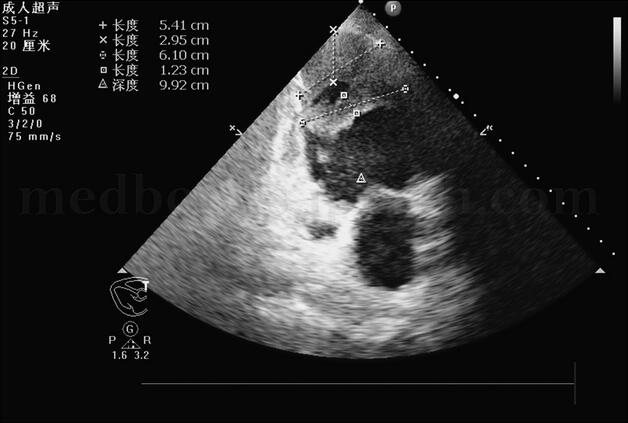

胸部X线片(图003‐1)示:肺水肿并双下肺感染改变;心尖部钙化,不除外室壁瘤可能;双侧胸腔积液,右侧叶间积液;右上肺高密度影。生化结果:心肌酶、肝肾功能正常。D‐二聚体:3129μg/L(0~300)。心电图(图003‐2)示:窦性心动过速,右束支传导阻滞,陈旧性前壁心肌梗死。超声心动图(图003‐3~图003‐5)显示室间隔破裂穿孔(因血栓封堵,无分流):室间隔中间可见两处回声缺失,直径均约为0.4cm,其左室面血栓形成。彩色多普勒:未见明确过隔分流。左室腔中间‐心尖段可见两块不规则形中低密度团块影附着,团块部分相互连接,两团块大小分别为5.4cm×2.95cm、6.1cm×1.23cm。

图003‐4 超声心动图2